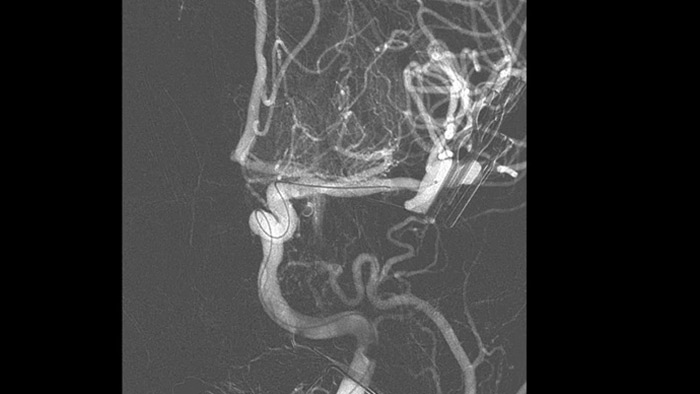

SmartCT Vaso permet de visualiser au-delà du caillot grâce à l’imagerie péri-procédurale de l’aspect des vaisseaux distaux dans les accidents vasculaires cérébraux ischémiques. SmartCT Vaso est une technique basée sur une acquisition Cone Beam CT à faisceau conique et une injection de produit de contraste intra-artérielle. Elle permet la visualisation au-delà du caillot avec l’imagerie péri-procédurale de l’aspect des vaisseaux distaux dans l’accident vasculaire cérébral ischémique. Grâce au remplissage rétrograde, les structures des vaisseaux avant et après le caillot deviennent visibles. SmartCT Vaso 3D Roadmap vous aide à visualiser les dispositifs de retrait de caillot.

SmartCT Roadmap fournit des références anatomiques permettant une navigation précise du fil-guide, du cathéter et du dispositif jusqu’au caillot.

Visualisation d’angiographie par soustraction numérique (ASN)

Les visualisations d’angiographie par soustraction numérique (ASN) de haute qualité vous permettent d’évaluer si vous avez retiré le caillot complet et si des morceaux de caillot ont été dispersés de manière distale dans le cerveau. Vous pouvez vérifier le rétablissement du débit sanguin dans la pénombre et contrôler les hémorragies péri-procédurales.